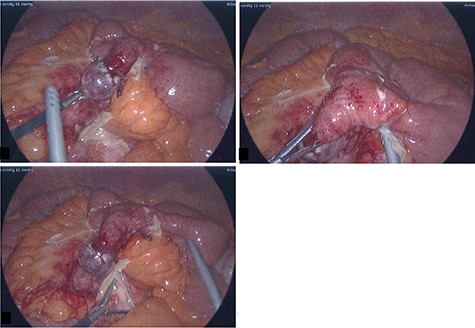

He was commenced on intravenous antibiotics and underwent an initial laparoscopy where an inflamed MD with local perforation was found with significant surrounding inflammation, a normal appendix was confirmed (Fig. 2). The decision was made to convert to a mini-laparotomy given the need for a small bowel resection with subsequent stapled side to side anastomosis. On macroscopic examination of specimen in the operating theater, a corn kernel was found obstructing the lumen of the diverticulum.

Intra-operative photos: acutely inflamed MD with a wide base and gangrenous tip, associated with significant surrounding inflammation.

The histology confirmed a small bowel diverticulum with no ectopic gastric or pancreatic tissue within it, full-thickness gangrenous necrosis of the wall with secondary perforation, abscess formation within the peridiverticular mesentery and acute fecal peritonitis. Fragmented vegetable material consistent with a seed of corn present within the distal diverticular lumen in the region of the perforation was reported.